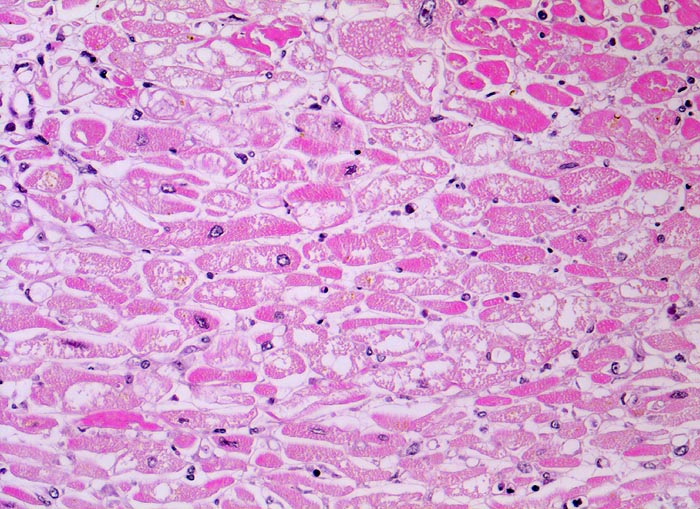

Myokardinfarkt und tubuläre Degeneration

Koagulationsnekrose der Myokardfasern: Fehlende Kernfärbung, Sarkoplasma hypereosinophil, homogen oder schollig. Muskelfasern mit erhaltenen Kernen und hellem vakuolisiertem Sarkoplasma mit Verlust der Myofilamente (=Holundermarkzellen =massive Glykogenspeicherung).

Diagnose eines Myokardinfarktes vor 4 Tagen.

Die hypoxisch bedingte vakuoläre (=tubuläre) Degeneration beruht auf einem Verlust der Myofibrillen und Glykogenspeicherung. Die zentral leeren Myokardzellen werden auch Holundermarkzellen genannt. Die veränderten Kardiomyozyten sind noch vital aber können sich nicht mehr kontrahieren. Das Auftreten der vakuolären Degeneration ist korreliert mit Herzinsuffizienz.